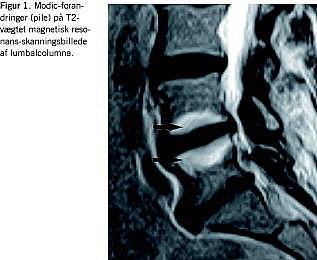

På rygområdet er det vist, at man ved magnetisk resonans (MR)-skanning kan diagnosticere og prognosticere prolapsforløb, f.eks. har »frie prolapser« et gunstigere forløb end protrusioner og inkomplette prolapser. Med MR-skanning kan man også diagnosticere inflammation af vertebrae nær degenererede disci (Modic-forandringer) (Figur 1 ), og samlet forklare rygsmerterne hos 30-50% af patienterne med varige gener.